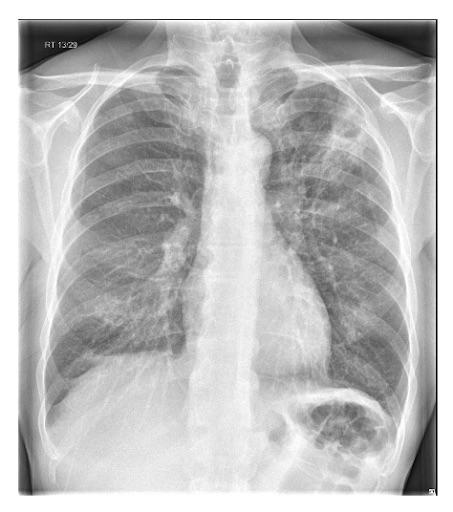

Un diagnóstico definitivo de NAC requiere evidencia de consolidación en la radiografía de tórax.[1][63][65][75] Realice una radiografía de tórax en todos los pacientes que se presenten en el hospital lo antes posible y dentro de las 4 horas posteriores al ingreso.[Figure caption and citation for the preceding image starts]: Radiografía de tórax posterior-anterior que muestra consolidación del lóbulo superior derecho en un paciente con neumonía adquirida en la comunidadDurrington HJ, et al. Recent changes in the management of community acquired pneumonia in adults. BMJ 2008;336:1429. [Citation ends].